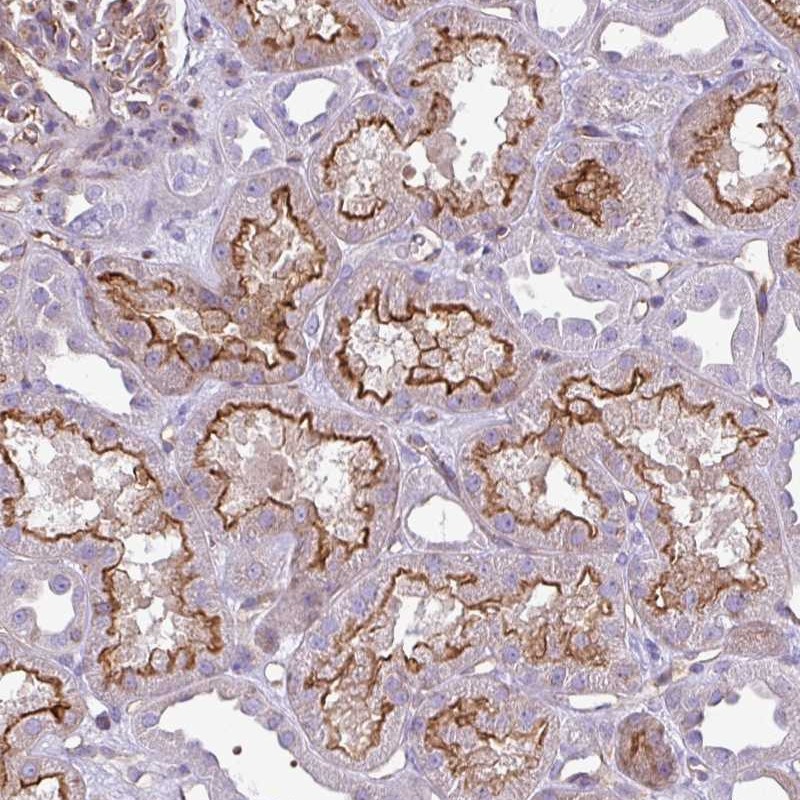

Immunohistochemical staining of human kidney shows strong membranous positivity in cells in tubules.